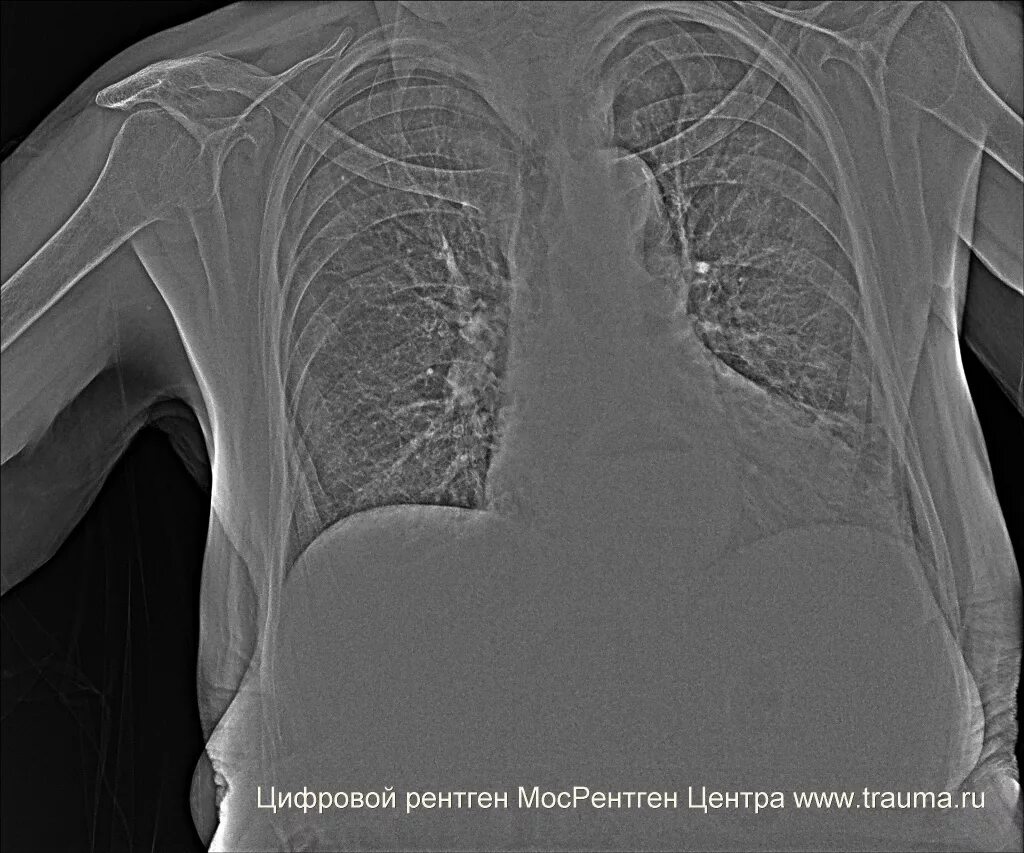

Аортокоронаросклероз легких что это такое